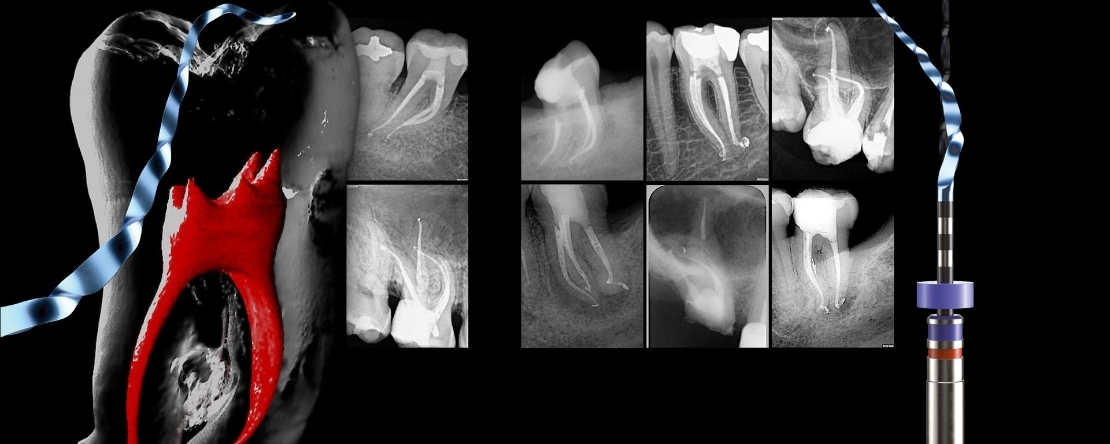

Abordagem de canais curvos mediante a instrumentação com tecnologia NiTi de ultima geração. Sistema RACE EVO®.